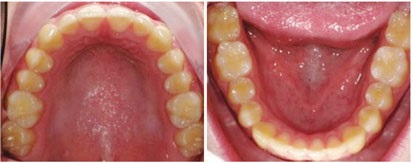

Figs. 3a-g: Initial records.

Fig. 3a

Fig. 3b

Fig. 3c

Fig. 3d

Fig. 3e

Fig. 3f

Fig. 3g